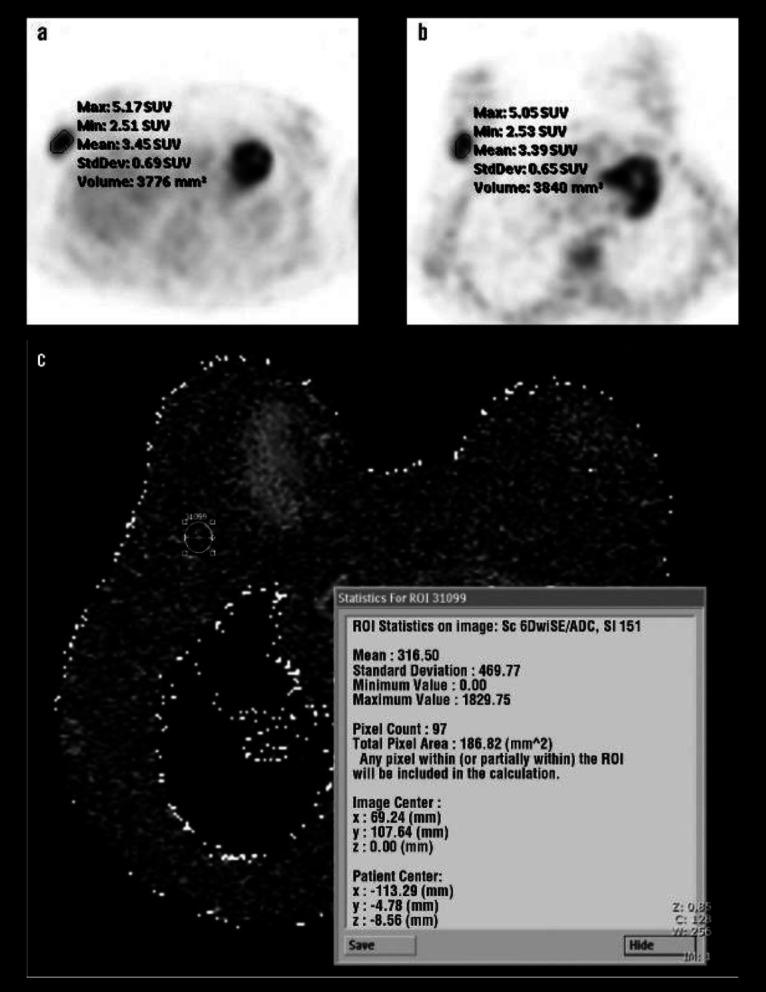

Breast carcinoma is the most common type of cancer in females. This study aims to compare fluorine-18-fluorodeoxyglucose (F-FDG) uptake pattern and apparent diffusion coefficient (ADC) value for the detection of the primary tumour and axillary metastases of invasive ductal breast carcinoma.

This study included 40 breast carcinoma lesions taken from 39 patients. After staging by positron emission tomography-computed tomography (PET/CT) and diffusion-weighted magnetic resonance imaging (MRI), breast surgery with axillary lymph node dissection or sentinel lymph node biopsy was performed.

Primary lesion detection rate for PET/CT and diffusion-weighted MRI was high with 39 of 40 lesions (97.5%). The sensitivity and specificity for the detection of metastatic lymph nodes in axilla were 40.9%, 88.9%, with F-FDG PET/CT scans and 40.9%, 83.3%, for dw-MRI, respectively. No significant correlation was detected between ADC and SUV or SUV ratios. Estrogen receptor (p=0.007) and progesterone receptor (p=0.036) positive patients had lower ADC values. Tumour SUV was lower in T1 than T2 tumour size (p=0.027) and progesterone receptor-positive patients (p=0.029). Tumour/background SUV was lower in progesterone receptor-positive patients (p=0.004). Tumour/liver SUV was higher in grade III patients (p=0.035) and progesterone receptor negative status (p=0.043).

This study confirmed the high detection rate of breast carcinoma in both modalities. They have same sensitivity for the detection of axillary lymph node metastases, whereas the PET/CT scan had higher specificity. Furthermore, ADC, SUV and SUV ratios showed some statistical significance among the patient groups according to different pathological parameters.